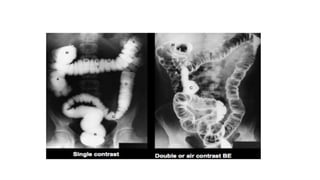

DOUBLE CONTRAST SINGLE CONTRAST

METHODS DOUBLE CONTRAST SINGLECONTRAST • The method of choice to demonstrate mucosal pattern. • The primary aim in a double contrast study is to achieve good mucosal coating. • Preferred in high risk patients- rectal bleeding, anemia, weight loss, family history of carcinoma / polyp, suspected IBD. • Contrast medium - high density barium suspension – 60-120% w/v and a kilo voltage of about 90 is used. • simpler, shorter and does not require rigorous maneuvers. • Preferred in very young, very old, sick and disabled patients. • In suspected obstruction and in evaluation of distal colon after colostomy • Contrast medium - low density barium suspension - 12-25% w/v, and a kilo voltage of 100 -110 is used.